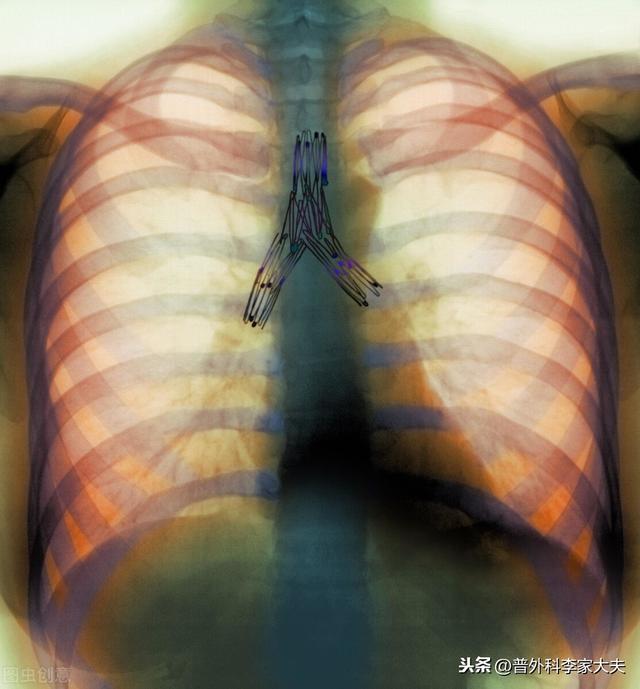

一般的に、ステージIの肺癌では術後補助放射線療法は行われないが、ステージIIおよびIIIAの患者では、補助化学療法と、必要に応じて補助放射線療法が考慮される。

I期肺がんの手術後の「集中治療」は可能ですか?特にIA期の患者には、化学療法は生存期間にとって有益ではなく、有害な副作用を増加させるので推奨されません。一方、IB期の患者は化学療法を "検討 "すべきです。

化学療法を恐れている人は多く、その恐怖は人々から聞いたり、インターネット上の情報は、空虚な話とは言えない、化学療法は多くの有毒な副作用がありますが、個人差があり、薬剤の更新、完璧な前処置などの状況は異なるが、大多数の人は肺がん手術後、4-6回の補助化学療法を完了することができます。補助化学療法は再発と転移を予防するための最も重要な手段である。

0期や1期の早期非小細胞肺がんの患者さんが、肺がんの真の根治切除である手術を受けた場合、術後補助化学療法やその他の標的療法は必要ありません。手術後に患者さんがしなければならないことは、肺がんの再発を防ぐことです。上記のように肺がんの発がん因子を取り除き、肺がんの定期的な経過観察・見直しがしっかり行われていれば、一般的には、この種の患者さんは術後半年に1回、2年以降は1年に1回、全身の検査を受けた方が安心です。

ステージ2、3の非小細胞肺がん患者の場合、肺がんの根治切除は行われている。しかし、理論的にも事実としても、本当の意味で肺癌が治癒したわけではなく、体内に残存する肺癌細胞が再発する危険性があることも明らかである。 そのため、現在の国内外の肺癌診断・治療ガイドラインから、これらの肺癌手術患者には、術後補助化学療法や分子標的治療などの総合的な治療を行うことが求められている。もちろん、術後化学療法をどのように行うか?比較的単純な言い方をすれば、肺癌診断・治療ガイドラインの原則に忠実に従うことを基本に、患者の実情に応じて微調整を行い、ガイドラインで紹介されている治療計画をより患者の状態に適したものにすることができる。また、上記のように肺がんの発がん因子を除去し、肺がんの定期的な経過観察・検診をしっかり行うことも必要であるが、前述のように肺がんの手術を受けた患者は体内に肺がん細胞が残存しているリスクが懸念されるため、それに対応する定期検診の間隔は短くせざるを得ず、一般的には1年目は3ヶ月に1回、2年目は6ヶ月に1回、2年目以降は1年に1回となる。主な検査項目は、胸部CT、腹部超音波またはCT、全身骨スキャン、いくつかの定期的な血液検査である。